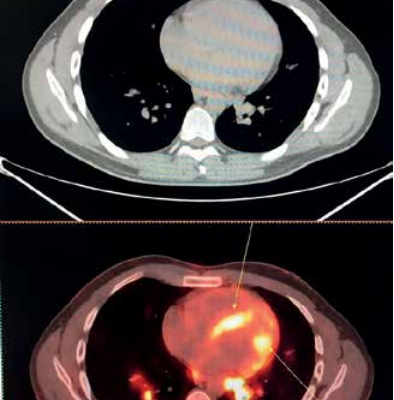

диагностика рака легких

ИИ в Пульмонологии: Как Нейросети Разглядывают Рак Легких на Ранних Стадиях, Спасая Жизни Мы живем в удивительное время, когда искусственный интеллект